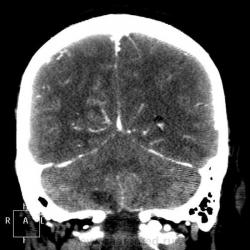

Мужчине 67 лет. У меня нет четкого мнения об изменении в правой затылочной доле. Ваше мнение?

"Непонятная штука в затылочной доле"-вероятнее артерио-венозная мальформация.Гиподенсная зона,прилежащая к ней-отдаленное последствие кровоизлиния из АВМ.

Может кавернома.

Склоняюсь к АВМ, прослеживается приводящий и отводящий сосуды. Не совсем понятно понижение плотности между сосудистыми петлями (может, коллега gar70 прав/а). Рекомендовала МРТ после выписки из сосудистого отделения (у нас такие вещи, что бы из сосудистых аномалий ни было, не оперируют).